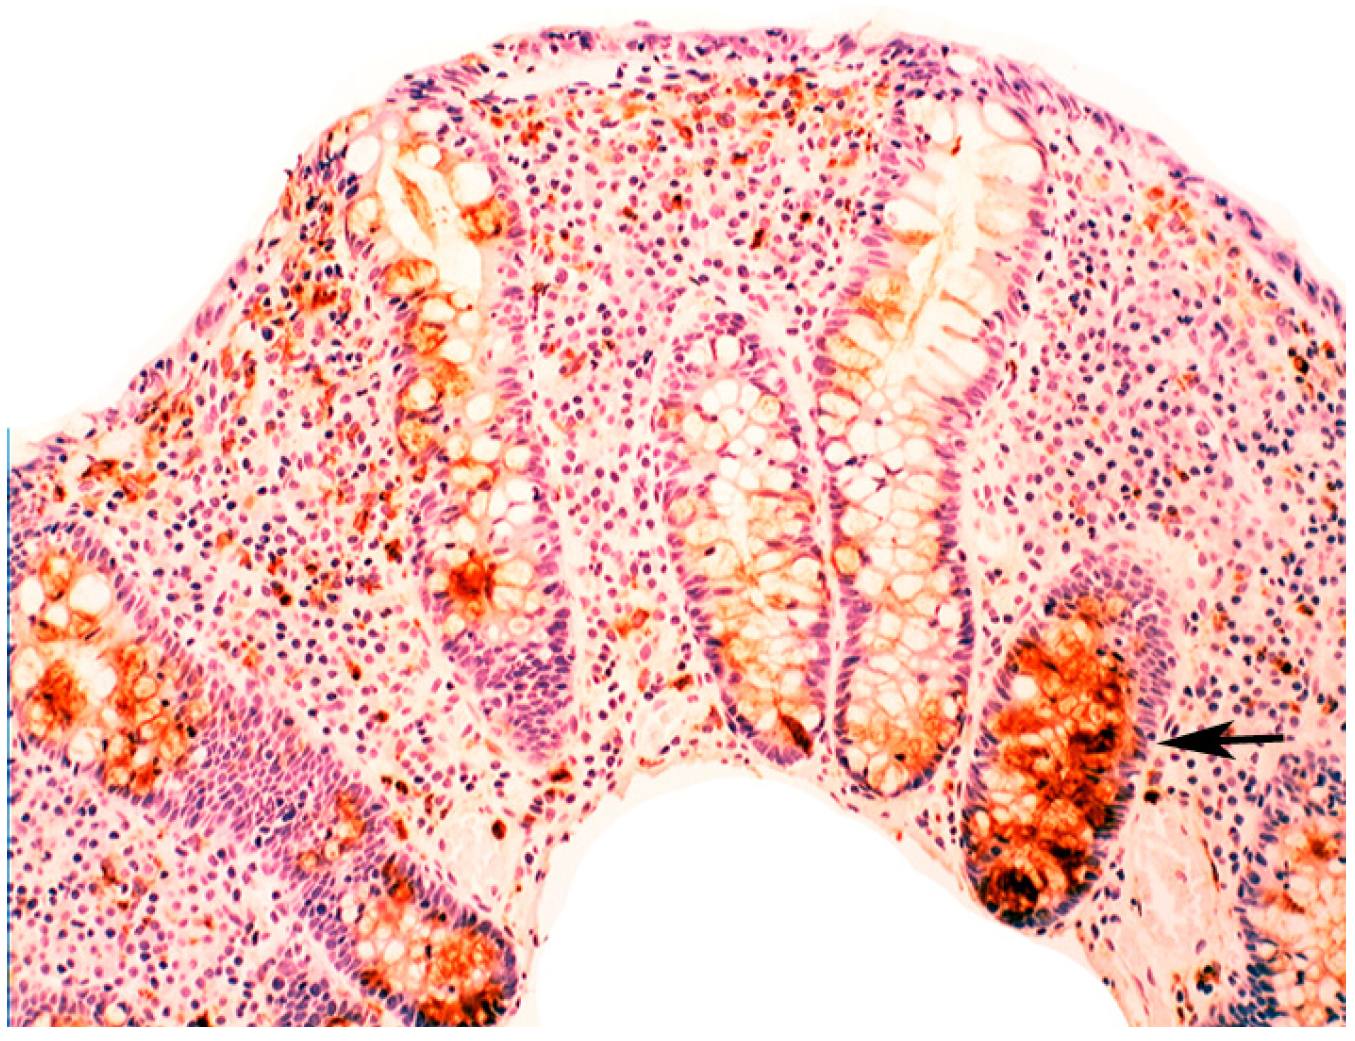

In chronic gastritis lysozyme is up-regulated in the neck region of the oxyntic mucosa, in antral pyloric glands (Figure 5) and in the surface-foveolar epithelium of the oxyntic mucosa [8]. In cases with in intestinal metaplasia, lysozyme is up-regulated in goblet cells (Figure 6), and in Paneth cells. In cases with autoimmune gastritis, lysozyme is up-regulated in pseudo-pyloric glands (Figure 7).

Figure 6.

Chronic gastritis with intestinal metaplasia. Left panel: Oxyntic (corpus) mucosa showing lysozyme expression in goblet cells and in mucus neck cells. Note absence of lysoyme expression in parietal cells in the lower part of the picture (below arrows); Right panel: Antro-pyloric mucosa showing lysozyme expression in goblet cells and in Paneth cells at the bottom of the crypts (arrows, lysozyme immunostain, ×10).